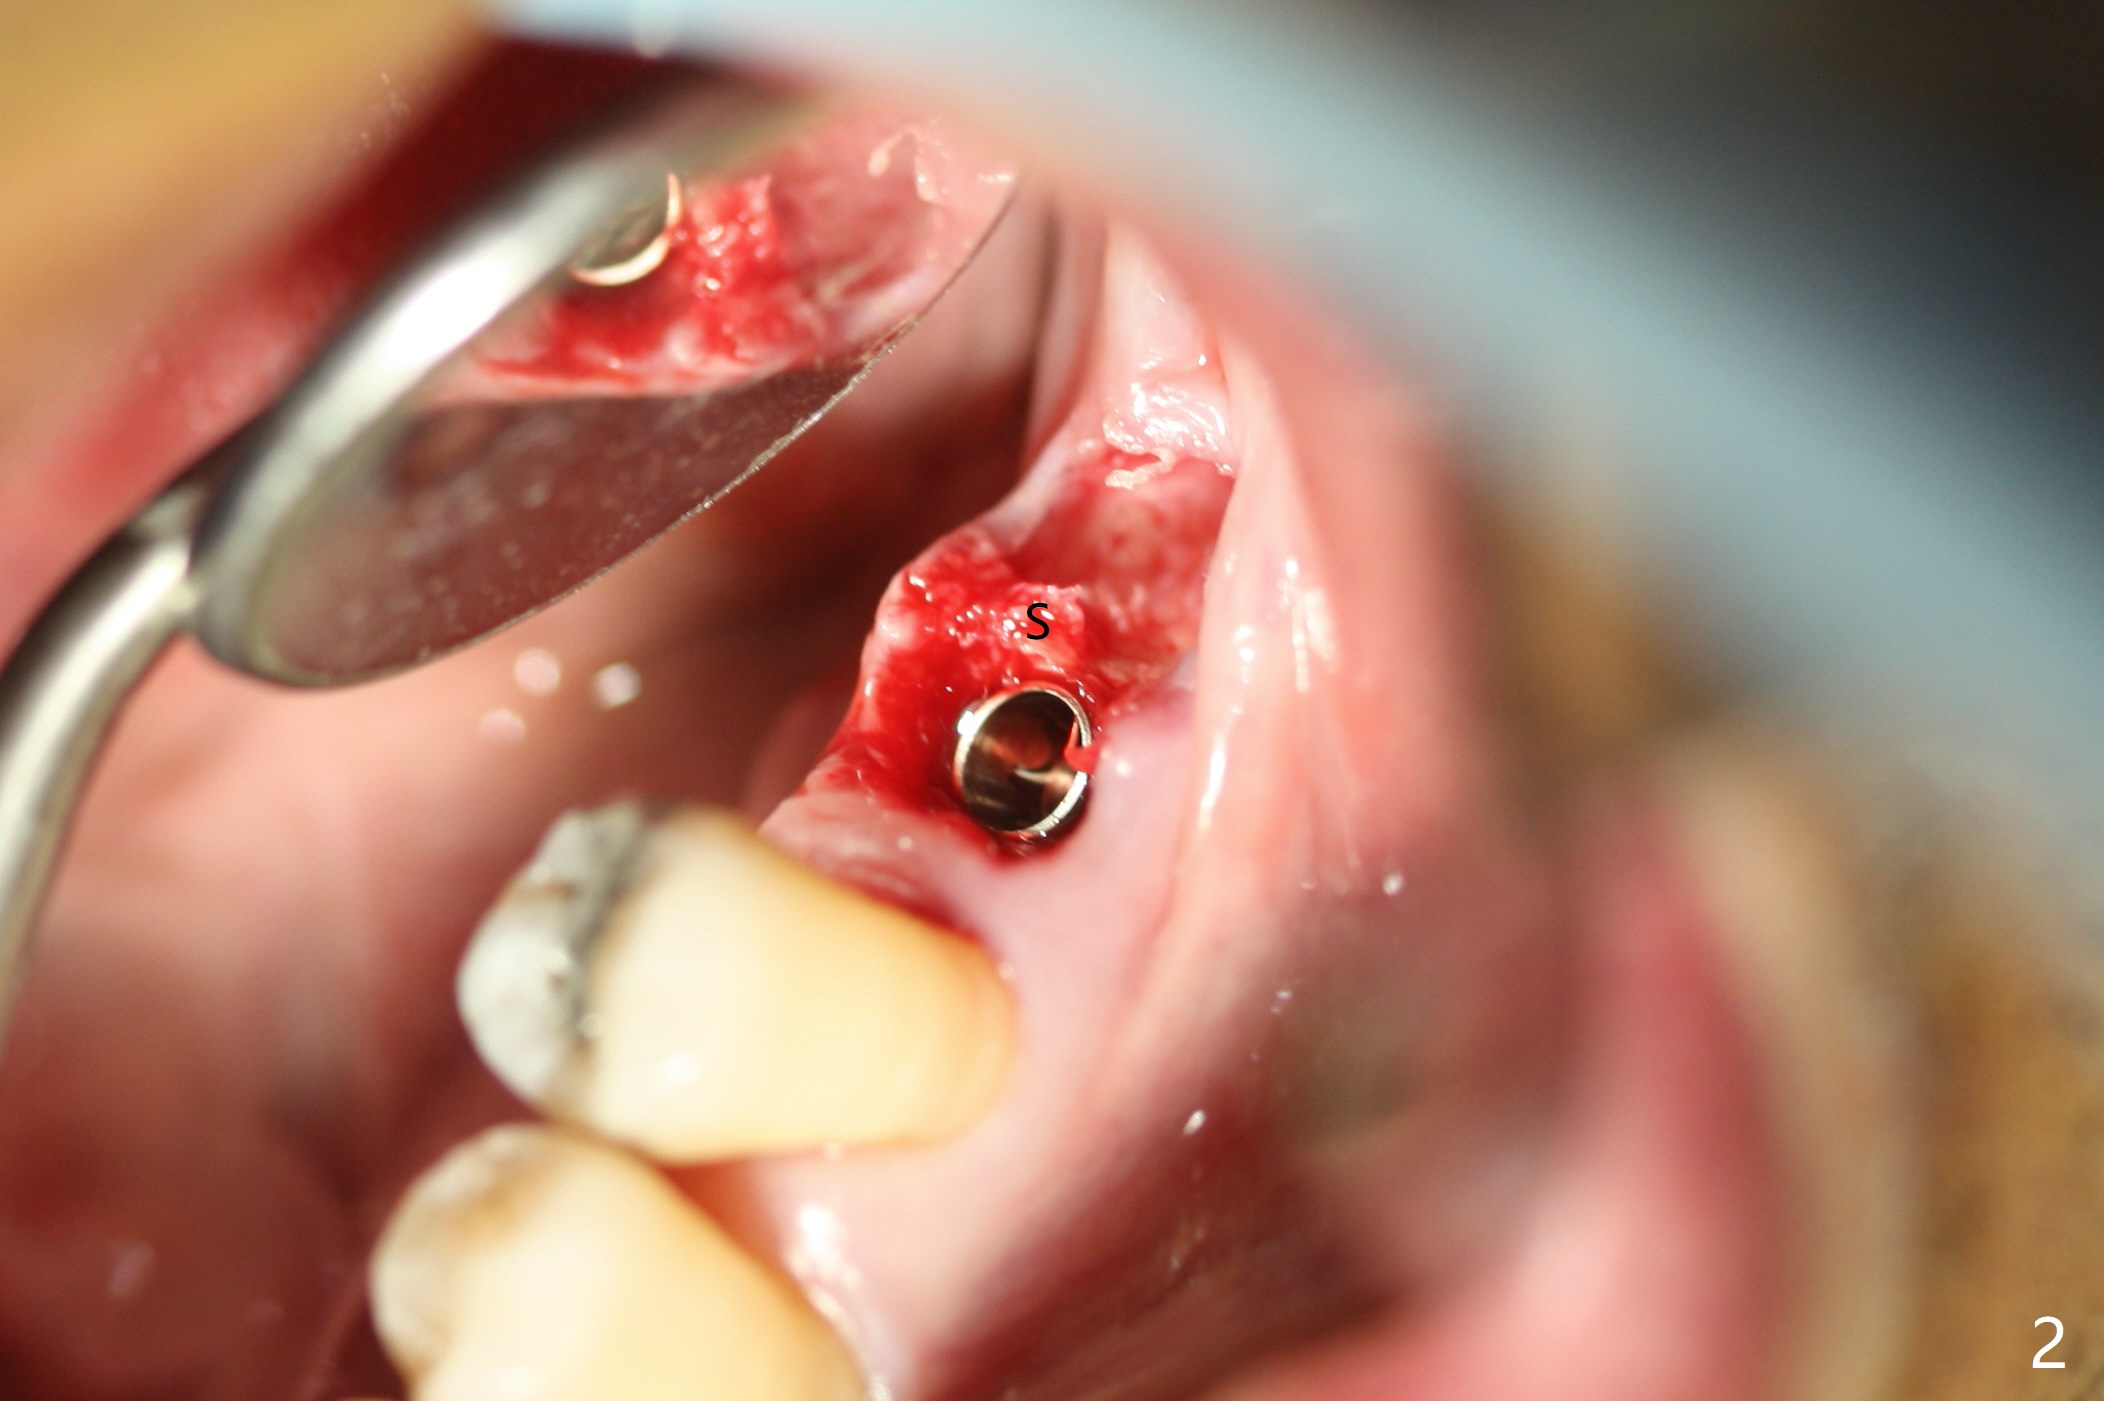

The guide does not arrive when the tooth #19 is extracted. Osteotomy is initiated free hand in the mesial socket as planned, slightly lingual, for 11.5 mm (Fig.1). Following sequential osteotomy, a 4.5x10 mm implant is placed subcrestal septally (Fig.2 S) and 2.3 mm from the neighboring apex (Fig.4). A 5.5x5(4) mm abutment is placed immediately and allograft is placed in the remaining sockets (Fig.4 *). An immediate provisional is fabricated to keep the graft in place (Fig.5 P; the most secure socket preservation).